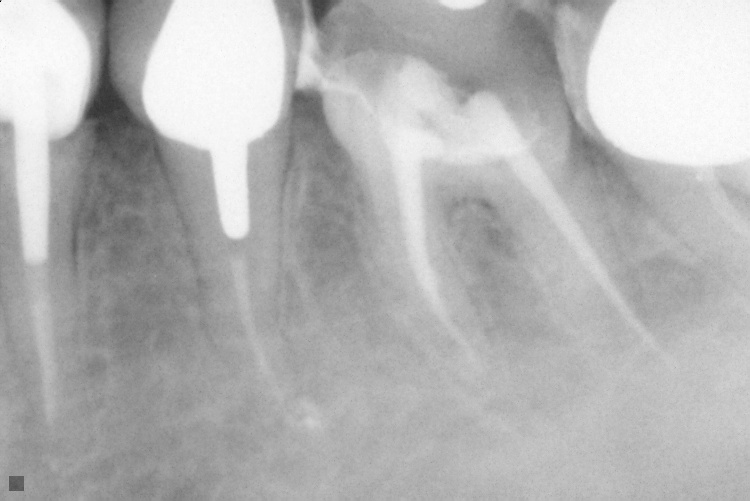

Name Last modified Size Description Parent Directory - IO000001.jpg 2020-07-28 14:20 84K IO000002.jpg 2020-07-28 14:20 82K IO000003.jpg 2020-07-28 14:20 85K IO000004.jpg 2020-07-28 14:20 82K IO000005.jpg 2020-07-28 14:20 84K